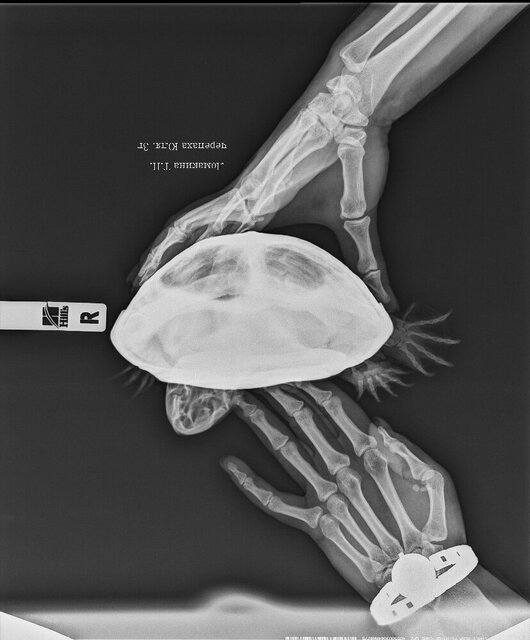

Поехала с этим к ветеринару, осмотрели и отправили на рентген, фото рентгена также прикрепила ниже. После рентгена врач сказал, что все у нас отлично и похвалил за хороший уход, порекомендовал снизить температуру на пару градусов на две недели, якобы судороги из-за этого пройдут. Я так и сделала, но судороги не прошли, как вы понимаете.

@moth здравствуйте! фото прикрепила, надеюсь теперь получше видно? печень и сердце даю почти каждый прием пищи, рыбу даю редко тк она очень мало съедает, выплевывает половину, пробовала разную давать. живет у нас 4 года уже, проблемы начались 2 года назад примерно